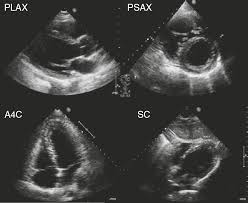

심장 초음파는 인체에 무해한 초음파를 이용해 실시간으로 이러한 심장의 움직이는 모습을 관찰할 수 있고 심장의 움직임과 구조, 혈류의 흐름, 판막의 이상 유무 등을 비침습적으로 관찰할 수 있는 검사법이라고 한다. 대부분의 심장 질환에 필수적인 검사며, 많은 심장질환에서 높은 정확도를 가진다고 한다.

심장 초음파로는 혈액의 역류를 막아주는 4개의 판막이 잘 열리고 잘 닫히는지, 구멍 등 이상 소견은 없는지, 혈액의 역류는 없는지 등을 확인할 수 있다고 한다.